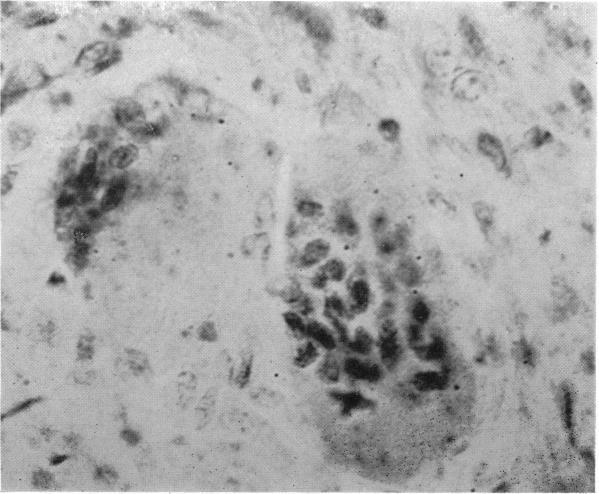

RECENT CLINICAL AND PATHOLOGICAL OBSERVATIONS ON GIANT-CELL MEDULLARY BONE TUMORS.

Ann Surg. 1916 Apr;63(4):454-63. doi: 10.1097/00000658-191604000-00008.